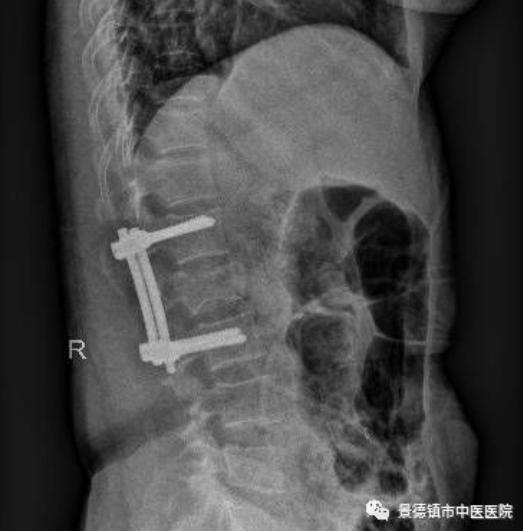

在臨近中午的時候,突然又來了一個腰部外傷的病人,患者L2椎體嚴(yán)重壓縮爆裂性骨折,脊髓受壓嚴(yán)重,下肢出現(xiàn)了麻木肌力減退等截癱癥狀?!摆s快做好術(shù)前檢查及準(zhǔn)備,這個需要急診手術(shù)”,一聲令下,所有人又要更加的忙碌了。于是,為了挽救一個面臨著癱瘓可能繼續(xù)加重的病人,下午又增加了一臺腰椎骨折急診復(fù)位并脊髓減壓手術(shù)了。同時也給手術(shù)室麻醉科、檢驗科等相關(guān)科室增加了假日的工作負(fù)擔(dān),在此也特別感謝大家的支持與配合。